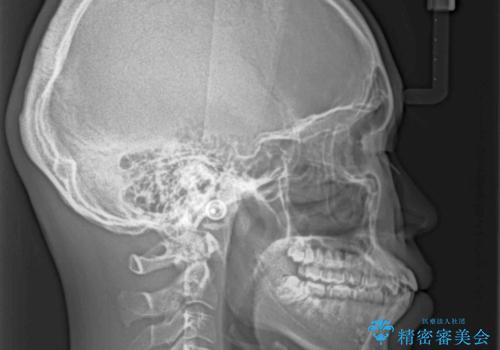

- 前歯のデコボコと口元の突出感を気にして来院された患者様です。

上下前歯がくちばしのように突出していたため、上下左右の第一小臼歯4本を抜歯し、ワイヤー装置にて矯正治療を行うこととしました。

左上は第二小臼歯が90度捻れており、状態が良くない歯であったため、左のみ第二小臼歯を抜歯することとしました。

第二小臼歯抜歯により治療期間が長くなることを了承いただき、治療を開始しました。

上顎骨に対して下顎骨がやや前方位に位置しているため、下顎前歯をあまり内側に移動させることができず、口元の突出感改善は期待以上にはならないと予測しておりましたが、満足いくの引っ込み具合となりました。